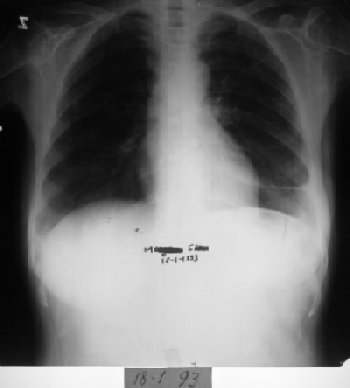

Röntgende belirgin düzelme. Tümör tamamen kayboldu.

Röntgende belirgin düzelme görüldü. Tedaviye devam edildi.

Tümörün tamamen kaybolduğu görüldü.